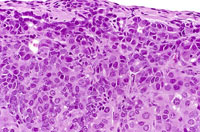

A discrete cholangiocarcinoma protruding above the natural surface of the liver. Higher magnification shows poorly formed glandular structures and a minimal scirrhous reaction.